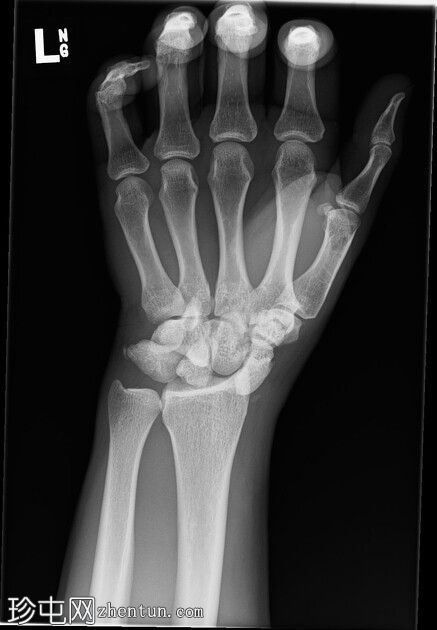

右腕

X光片

斜位

前后位:舟月骨间隙增宽,月骨呈三角形。侧面显示头状骨与月骨背侧脱位,月骨与桡骨远端保持正常排列。符合月骨周围脱位的特征。无合并腕骨、桡骨或尺骨骨折。腕部软组织肿胀。